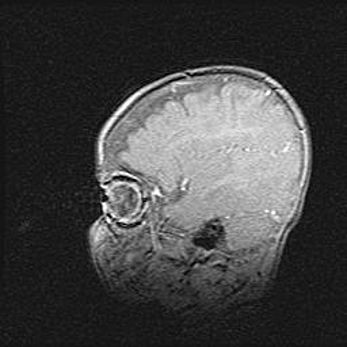

Подострая гематома правой гемисферы мозжечка.

Наружная гидроцефалия.

Возраст: 15 дней

Вес: 3100 г

Пол: женский

Окружность головы: 37 см

Срок гестации: 35-36 недель

При открытой наружной форме гидроцефалии у новорожденных расширяются и переполняются субарахноидные пространства.

Кровоизлияния в мозжечок имеют две клинико-анатомические формы: полушарные гематомы и кровоизлияния в червь.

К появлению этой патологии может привести: повреждения головного мозга, возникающие в результате асфиксии и гипоксии плода при беременности, или травмы во время родов. Редко гематома мозжечка может быть результатом первичной коагулопатии и сосудистой мальформации, диссеминированном внутрисосудистом свертывании, изоиммунной тромбоцитопении.